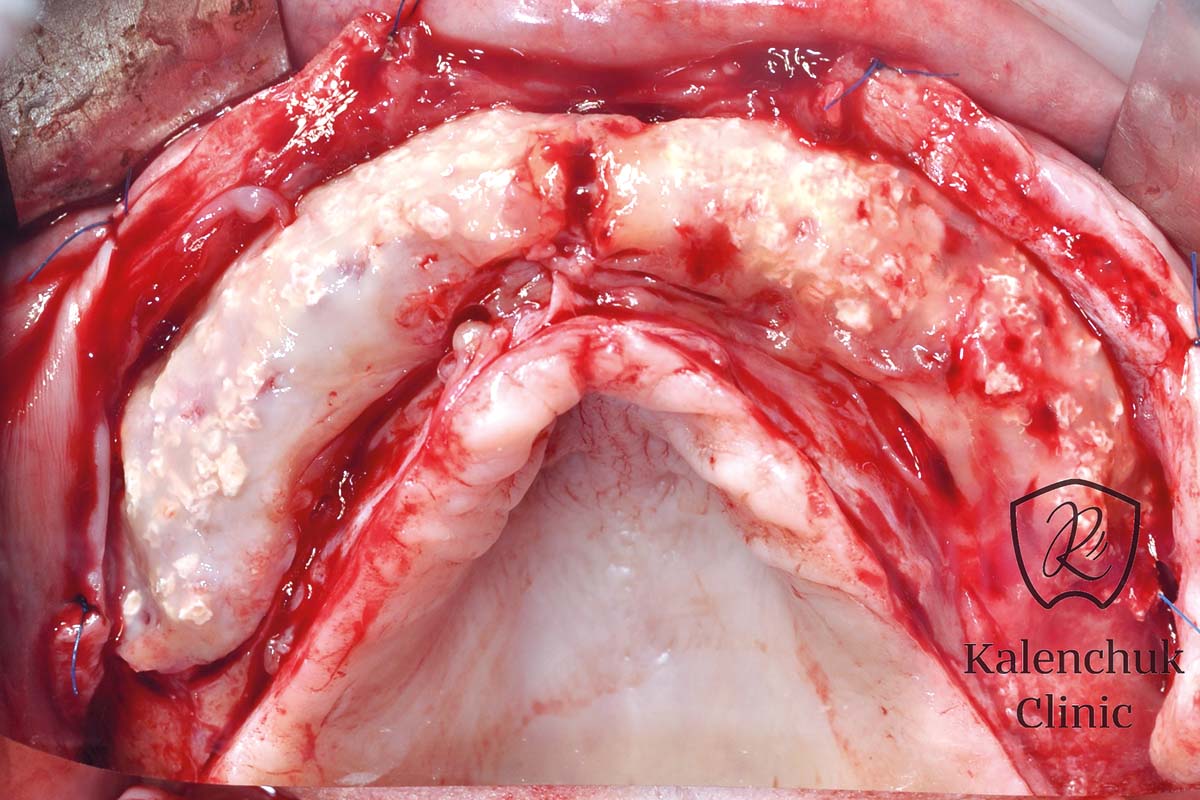

OTEVŘENÉ HOJENÍ U ALVEOLÁRNÍHO HŘEBENE A LŮŽKA PO EXTRAKCI

Vzhledem k tomu, permamem® mohou být použity k otevřenému hojení extrakčních ran, nebo při augmentaci alveolu. uzávěr primární rány je vynechán a jsou zachovány kontury měkkých tkání. Zlepší se estetický výsledek, protože nechirurgické odstranění membrány po době hojení vynechává potřebu velkých chirurgických řezů. Po odstranění permamem ®, je primární proces hojení a reepitelizace regenerované měkké tkáně dokončen přibližně za jeden měsíc. Ochrana lůžka po extrakci, nebo hřebene umožňuje údržbu architektury a kontur měkkých tkání, protože není vyžadováno žádné primární uzavření rány. Vzhledem k chybějícímu uzávěru chlopně nebude mukogingivální linie přemístěna a připojená / keratinizovaná gingiva bude zachována. Nechirurgické odstranění membrány po době hojení vynechává potřebu velkých chirurgických řezů (řezy s vertikálním uvolňováním), což zlepšuje estetiku.

APLIKACE, FIXACE, VIDITELNOST